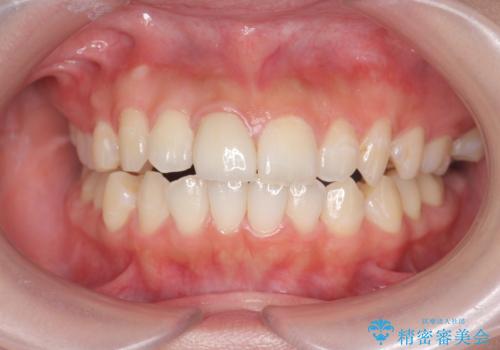

周囲の歯の色調に調和した審美性の高いセラミッククラウンを製作することができました。

- 13.2万円(ジルコニアクラウン・仮歯)費用は治療当時の料金となります